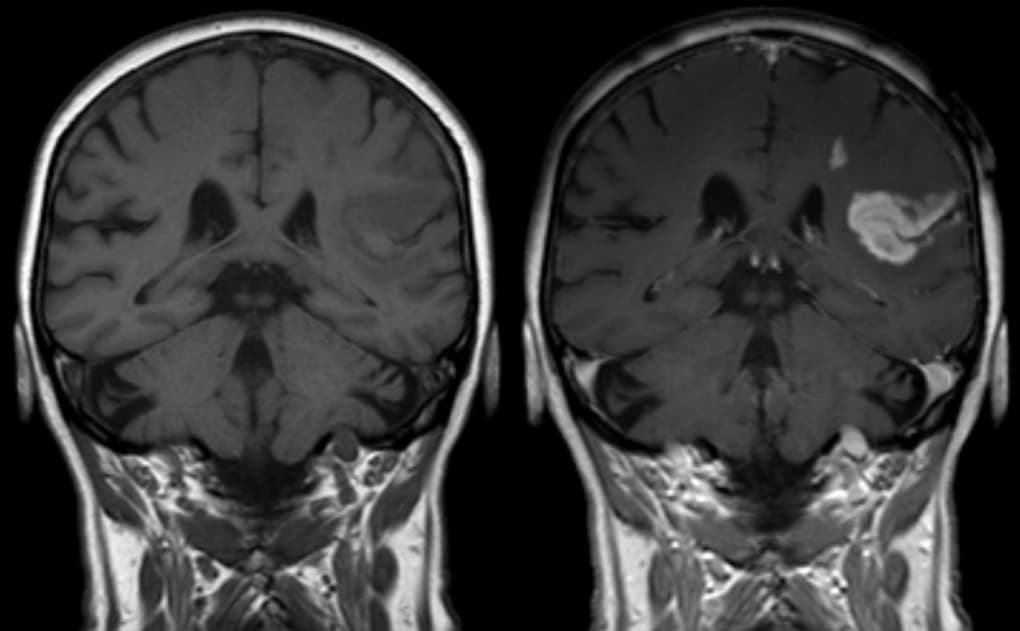

Beyin hasarı ilk aşamada bilgisayarlı tomografi (BT) ile görüntülenir. Beyin içi kanama, ödem, fıtıklaşma gibi ölümcül olabilecek sorunların belirtileri yönünden BT incelenir.